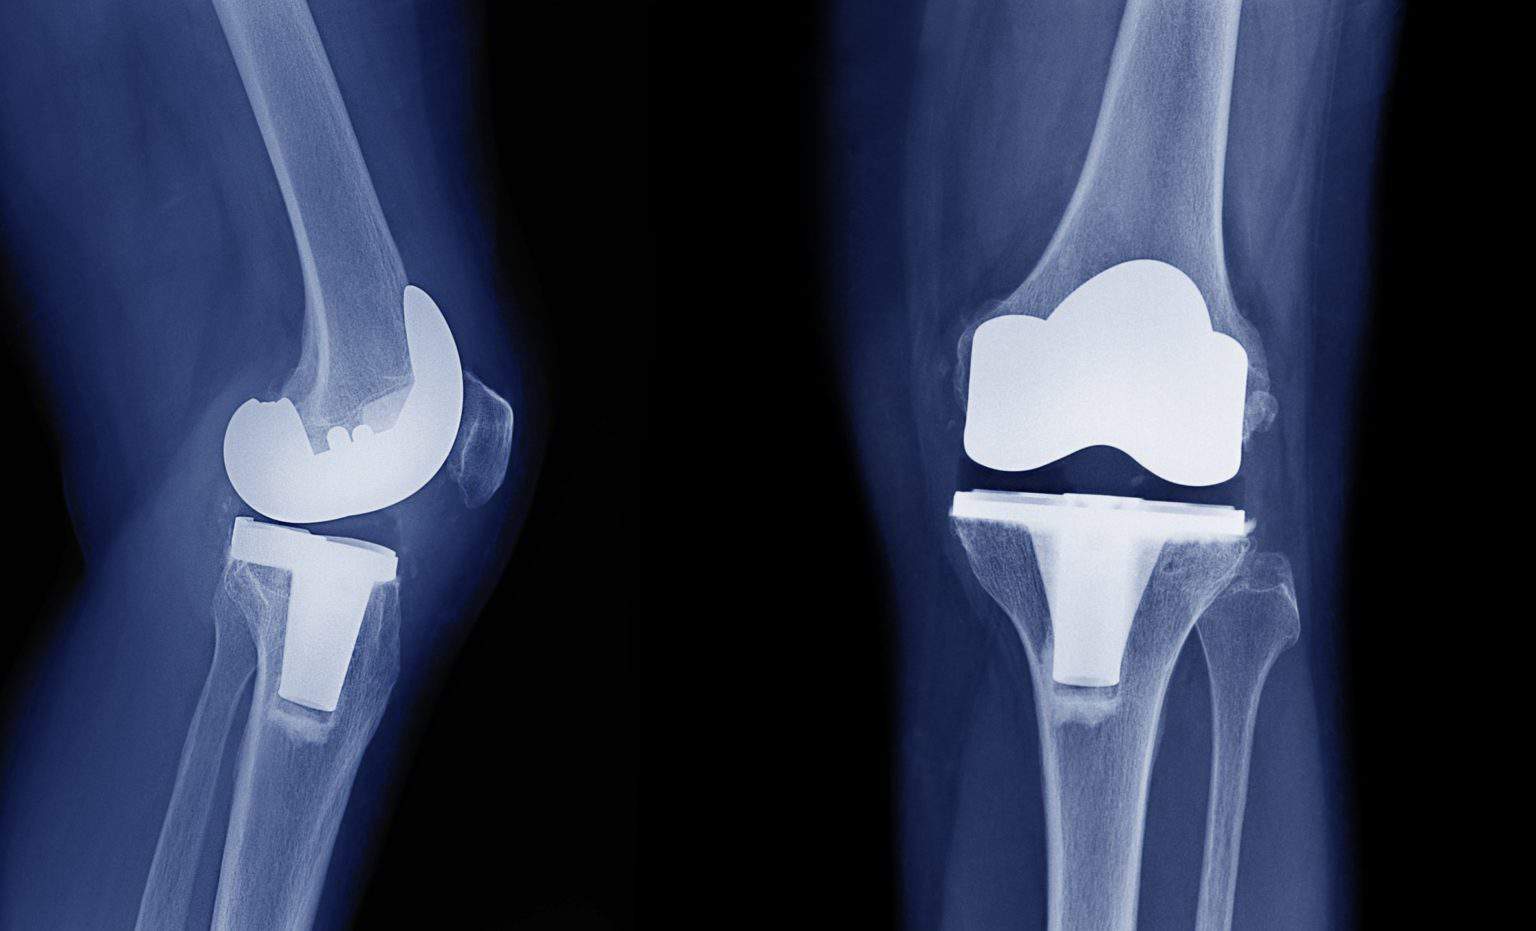

Alternative To Metal Knee Replacement . Its biocompatibility gives utility in medical implant manufacture, commonly spinal cages, dental components, and more recently,. Sometimes a knee replacement is considered too risky or too early to be recommended. All ceramic knee implants have several potential. What are the advantages of all ceramic total knee replacement? Thinking about a total knee replacement? Knee replacement is an operation to remove the arthritic parts of the knee and replace them with an artificial joint made of metal and plastic. In unicompartmental knee replacement (also called partial knee replacement) only a portion of the knee is resurfaced with metal and plastic components. These alternatives could help alleviate your knee pain. Within one year, the defect is. There are a few different kinds of knee implants that are used in this procedure.

Knee replacement is an operation to remove the arthritic parts of the knee and replace them with an artificial joint made of metal and plastic. Within one year, the defect is. Its biocompatibility gives utility in medical implant manufacture, commonly spinal cages, dental components, and more recently,. Thinking about a total knee replacement? There are a few different kinds of knee implants that are used in this procedure. All ceramic knee implants have several potential. Sometimes a knee replacement is considered too risky or too early to be recommended. What are the advantages of all ceramic total knee replacement? These alternatives could help alleviate your knee pain. In unicompartmental knee replacement (also called partial knee replacement) only a portion of the knee is resurfaced with metal and plastic components.